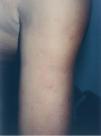

Un varón, de origen mexicano, adoptado, por lo que no se conocen sus antecedentes familiares y entre cuyos antecedentes personales destaca la presencia de una betatalasemia minor, había presentado a los 4 años de edad lesiones faciales que fueron diagnosticadas de LED crónico. Los padres habían rechazado tratamiento, y no se realizó seguimiento clínico. A los 13 años consultó por la aparición desde hacía un año, en tórax y brazos, de lesiones redondeadas, profundas, dolorosas a la palpación. Negaba fiebre, artralgias, aftas orales u otra sintomatología asociada. A la exploración se observaba la presencia, en cara anterior del tórax y parte proximal de extremidades superiores, con carácter bilateral y tendencia simétrica, de nódulos redondeados, bien delimitados, cubiertos unos de piel de coloración normal o rosada, con discreta depresión superficial y otros por piel eritematosa violácea, con escamas adheridas en su parte central (fig. 1). En la región facial se apreciaban placas redondeadas, con borde edematoso eritematoso violáceo y centro discretamente atrófico con gruesa escama adherida y tapones córneos (fig. 2).

Fig. 1.—Nódulos en parte proximal de brazos, cubiertos por piel rosado-violácea, con fina escama y zonas atróficas deprimidas residuales.